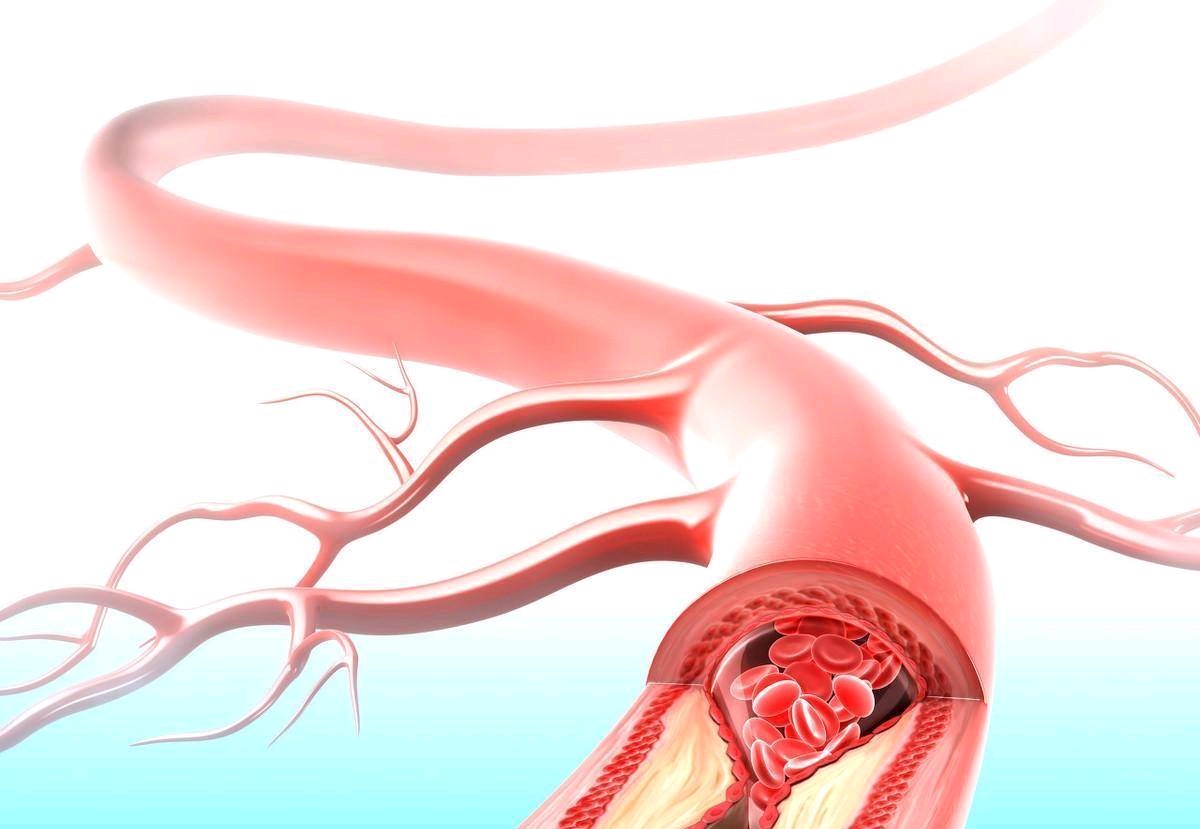

颈动脉从结构上分为内膜,中膜,外膜,三层膜,颈动脉受损时从动脉内膜开始。比如,长期的高血压、高血糖使细胞受损,血管内皮上出现小的破口,血液中的低密度脂蛋白大量的聚集,大量的巨噬细胞就来吞噬这些物质,这些吞噬细胞受不了发生坏死。在局部形成脂质团块,形成了斑块,斑块经过一段时间形成包膜,又叫纤维帽,纤维帽厚度和结实程度决定斑块的稳定性。

不稳定斑块有薄的纤维帽,大的且富含脂质的坏死,核心斑块内新生血管形成斑块,内出血伴有活动性炎症,斑块容易破裂,形成血栓。

斑块周边内部呈高密度的点状或线状增强,说明是不稳定易损的斑块,容易脱落。

高血压、高血糖的作用下可以使斑块破裂,一旦破裂,血液中起凝固作用的血小板就聚集在一起形成血栓,血栓可以从斑块上脱落,随着血液到处流动,堵塞血管,发生心梗、脑梗等。所以长的斑块为血栓发生创造了条件,是发生心脑血管疾病的高危因素。